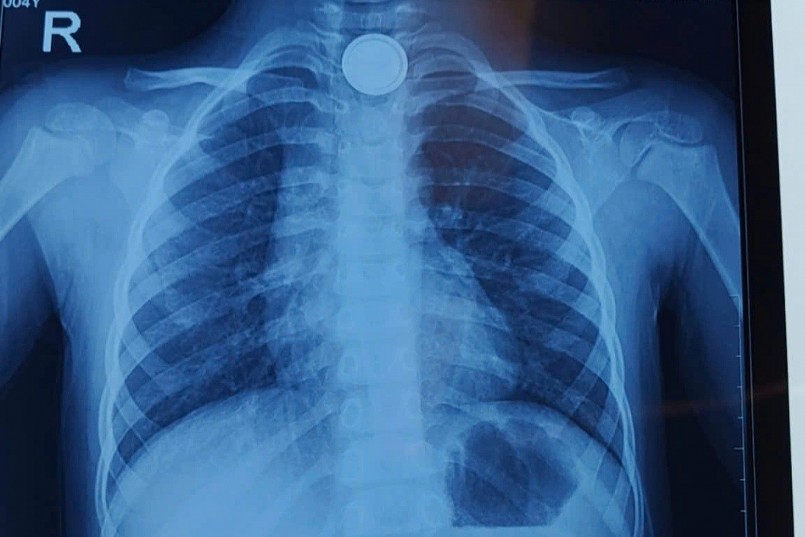

| Vị trí pin cúc áo trong cổ bệnh nhi (Ảnh: Bệnh viện cung cấp). |

Cụ thể, vào lúc 14h cùng ngày, bé V. vô tình nuốt phải pin cúc áo. Ngay sau đó, gia đình nhanh chóng đưa bé đến bệnh viện gần nhà, chụp X-quang phát hiện dị vật mắc ở thực quản ngang mức xương đòn.